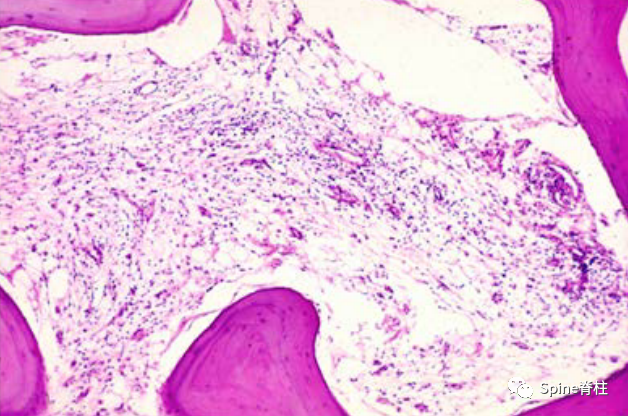

图 2. 具有纤维血管成分和增厚的骨小梁的 MC-1 的组织学 H&E 染色